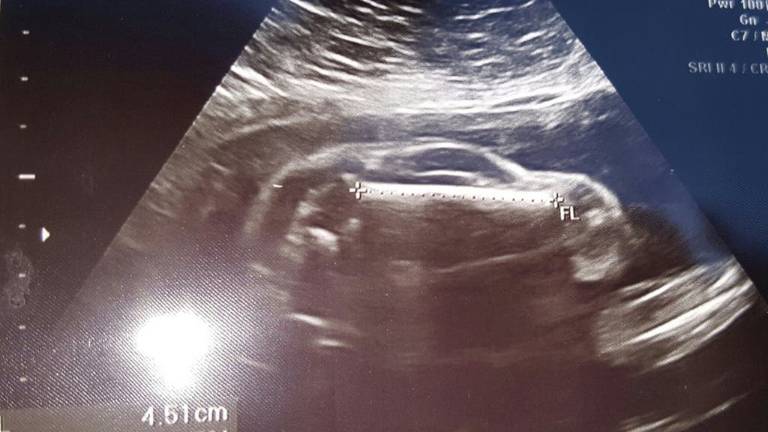

¿Un bebé o un auto deportivo? La sorpresa que dejó un ultrasonido

Uno de los momentos más emocionantes para una pareja es conocer el sexo de su hijo. Sin embargo, una pareja se llevó una gran sorpresa al mirar el monitor y ver que lo que mostraba el ultrasonido.

Lejos de parecerse a un bebé, la pantalla mostraba lo que parecía ser un auto deportivo dentro del vientre de la mujer, que tenía 24 semanas de gestación.

La imagen del ultrasonido mostraba una misteriosa silueta con ruedas, un techo inclinado, una ventana e incluso algo que se asemeja a un pequeño volante.

La curiosa imagen, que se viralizó rápidamente, fue compartida por el padre del bebé en Reddit con el siguiente mensaje: “Mi mujer está embarazada de un auto deportivo”.